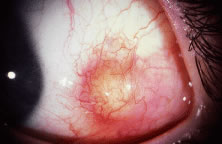

The globe is stabilized with a 0.5-mm-toothed Castroviejo forceps (Figs. 70 and 71). A mattress stitch with a double-armed 6-0 synthetic absorbable suture is placed through the most inferior portion of the insertion. The second needle is passed 1 mm below the central portion of the insertion. The initial penetration of the needle is just anterior to the insertion, and a secure bite is taken of the former insertion so that the needle exits just posterior to the old insertion. The needle is then passed underneath the Jameson resection clamp through muscle tendon, and the two sutures are held with a bulldog clamp to keep them separate from the sutures that are later passed through the upper pole of the insertion. Figure 71 shows the sutures being tied. This maneuver will effectively bring the resected muscle tendon up so that it can be reinserted at the insertion. Once the muscle is tied securely, the Jameson resection clamp is released and then advanced to the cut end of the insertion (Fig. 72). Under direct visualization, a Westcott scissors is used to trim the excess muscle stump. Care is taken to leave at least 1 mm of muscle tendon in front of the two sutures that secure the muscle to the insertion. After the muscle stump has been inspected, the conjunctiva is advanced back to the limbus (Fig. 73). Two 8-0 collagen sutures are used to secure the conjunctiva at the limbus. The small open radial portion of the incision will heal without suture closure. If the surgeon “buries the knots” under the conjunctiva near the limbus, the patient will have less foreign body sensation. Figure 74 shows the eye immediately after a recess-resect procedure. The conjunctiva should be smooth at the limbus to prevent disruption of the tear layer and formation of dellen. The eye is not patched. Antibiotic drops or antibiotic-steroid drops may be used at the discretion of the surgeon.